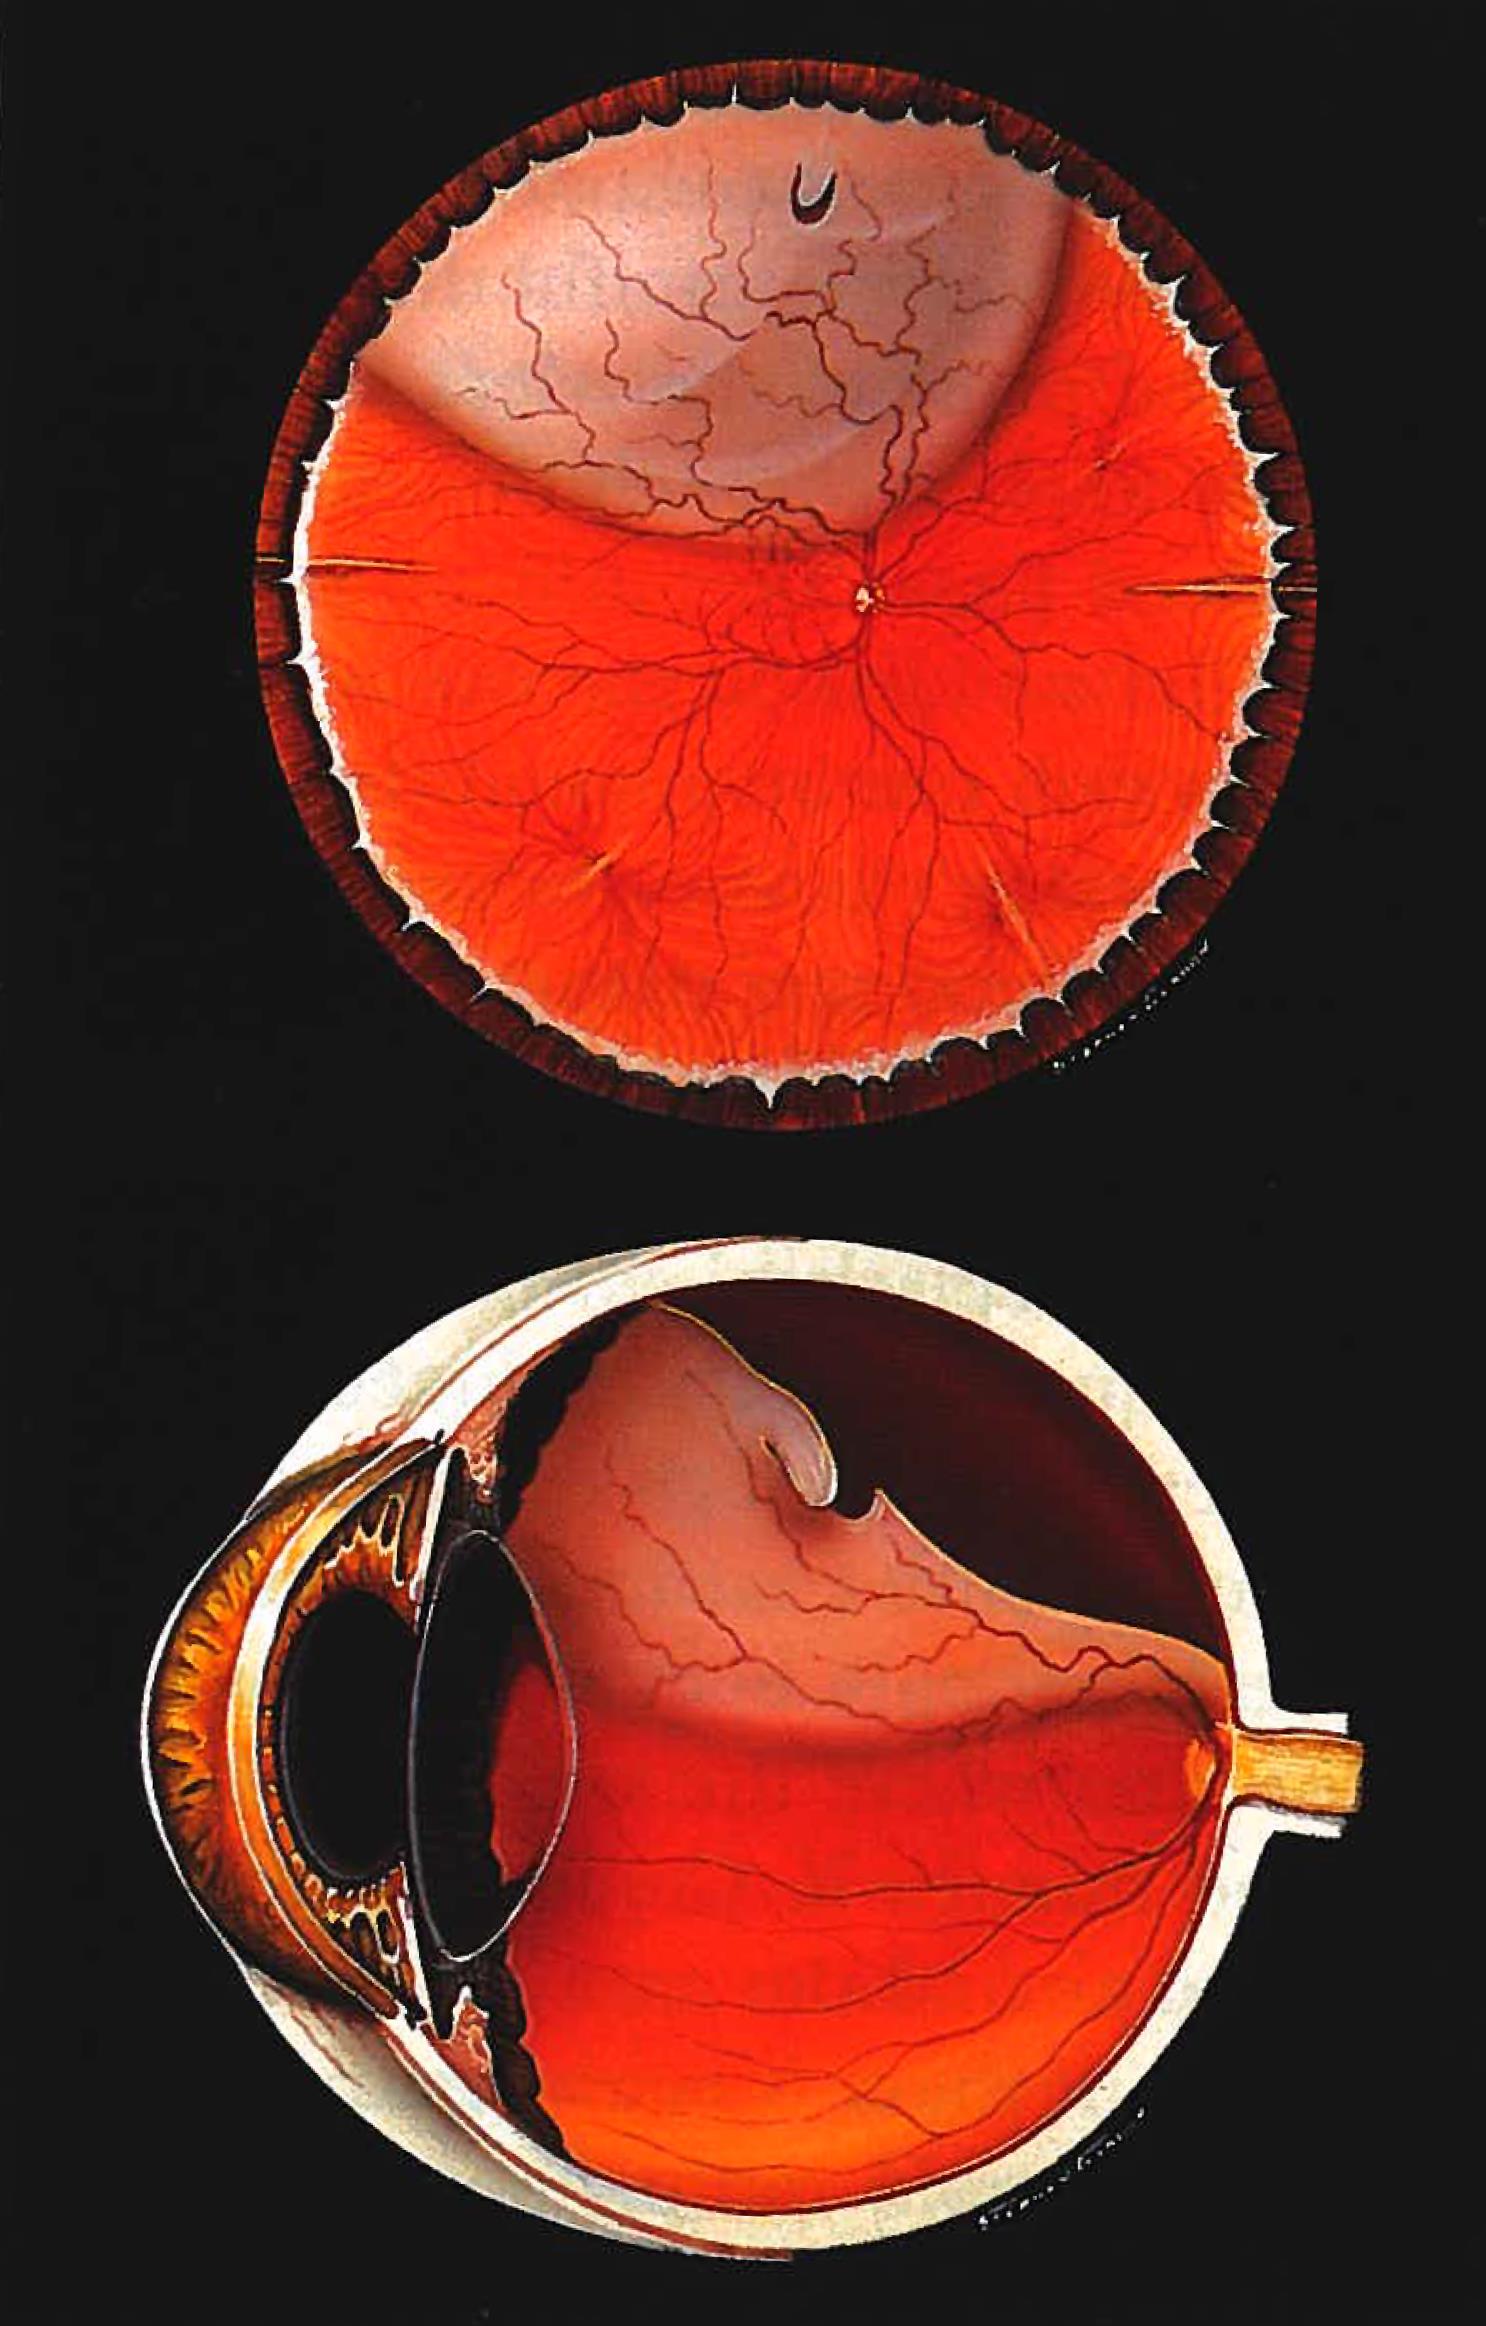

Vitrectomy And Vitreoretinal Eye Surgery Vitreous Hemorrhage Surgery

https://i.pinimg.com/originals/04/eb/63/04eb63b6d2fb52dbbffdc0bc1f577640.png

Retinal Detachment Surgery Detached Retina Treatment

https://www.retinacareflorida.com/wp-content/uploads/2021/04/RD2.jpg

Vitrectomy And Vitreoretinal Eye Surgery Vitreous Hemorrhage Surgery